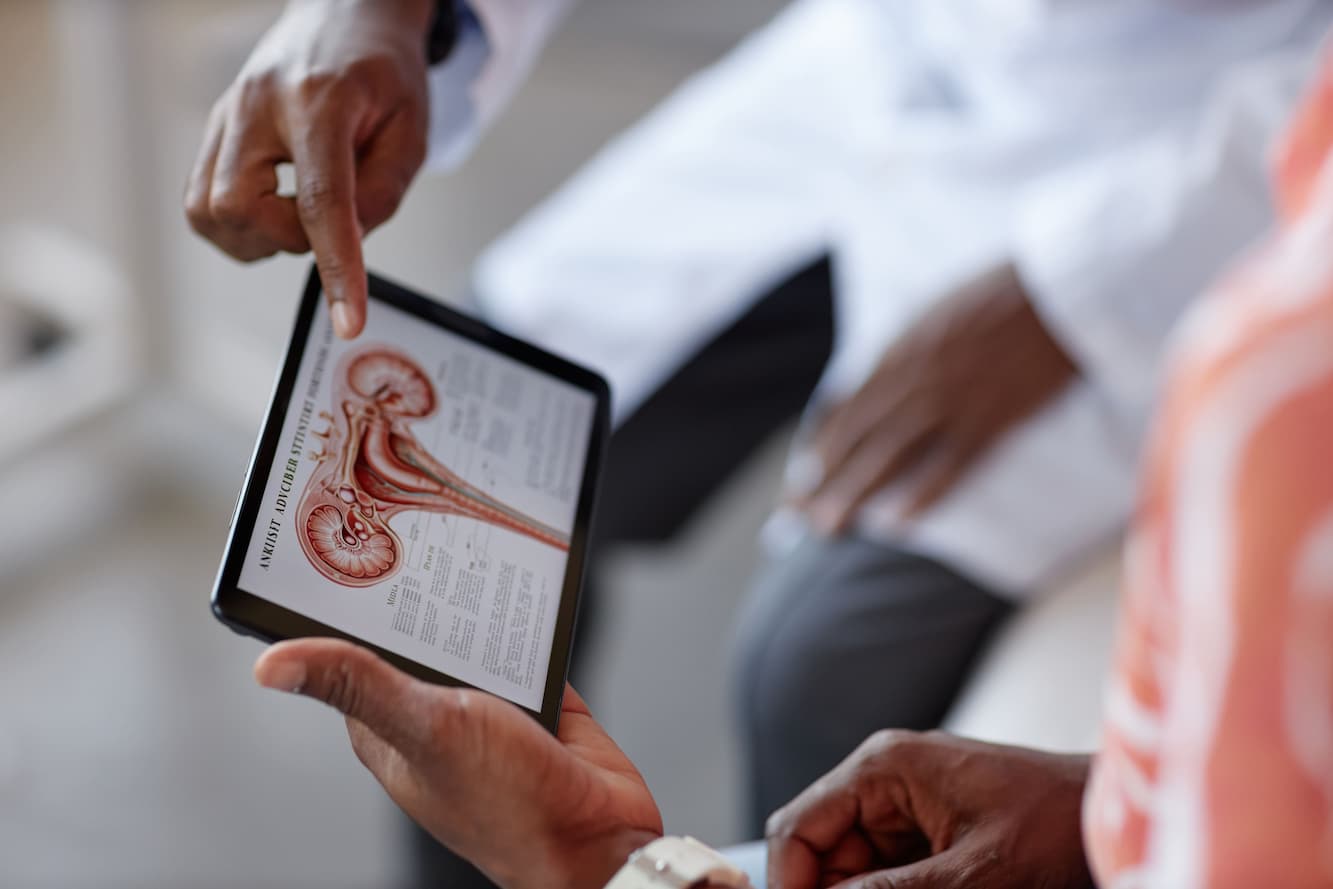

Urology is dedicated to maintaining the health of the urinary system. We work alongside esteemed urologists from our partner hospitals, who are committed to excellence and equipped with advanced technology.

Urology is dedicated to maintaining the health of the urinary system. We work alongside esteemed urologists from our partner hospitals, who are committed to excellence and equipped with advanced technology.